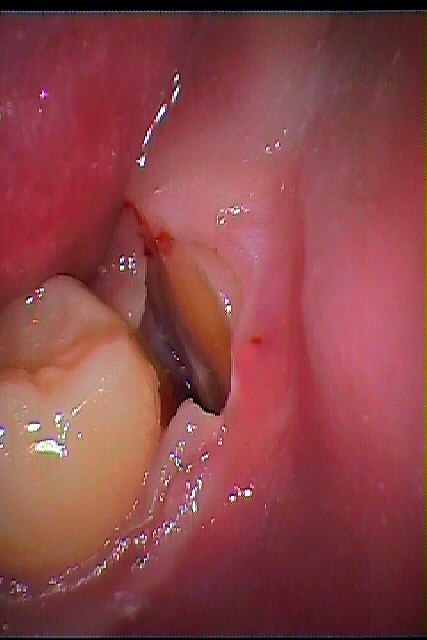

左下の水平埋伏歯の抜歯 難抜歯|お知らせ |広島市安佐南区の歯科医院 左下の水平埋伏歯の抜歯 難抜歯 トップ お知らせ・ブログ お知らせ 左下の水平埋伏歯の抜歯 難抜歯 左下の水平埋伏歯の抜歯 難抜歯 こんな親知らずになります 少しだけ見えています このように大きな親知らずが横たわっています パノラマレントゲンにて 歯冠部を分割抜歯しています 分割後になります ほぼ出血はありません 抜歯後縫合して終了となります このように抜歯できました 縫合して終了となります Web診療予約 初めての方へ 選ばれ続ける理由 院内設備について 歯が痛いしみる一般歯科 歯がぐらぐらする歯周病 健康な歯を保ちたい予防歯科 子供の虫歯予防をしたい小児歯科 銀歯をセラミックに審美歯科 白い歯を目指しませんか?ホワイトニング 矯正専門医がいるので安心矯正歯科 抜けた歯を補いたいインプラント・入れ歯 医院案内 スタッフ紹介 メリィハウス歯科クリニックオフィシャルホームページ ラベンダー歯科クリニックオフィシャルホームページ お知らせ・ブログ ホーム 診療科目 一般歯科 歯周病治療 予防治療 小児歯科 審美治療 ホワイトニング 矯正歯科 入れ歯・インプラント マウスピース矯正 初めての方へ 院長・スタッフ 設備紹介 医院案内・アクセス メニューを閉じる